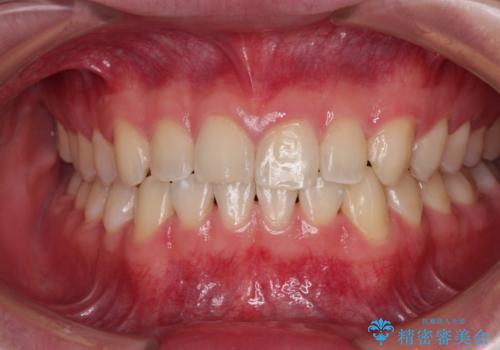

【インビザライン】マウスピース矯正希望。

担当医 河口智英